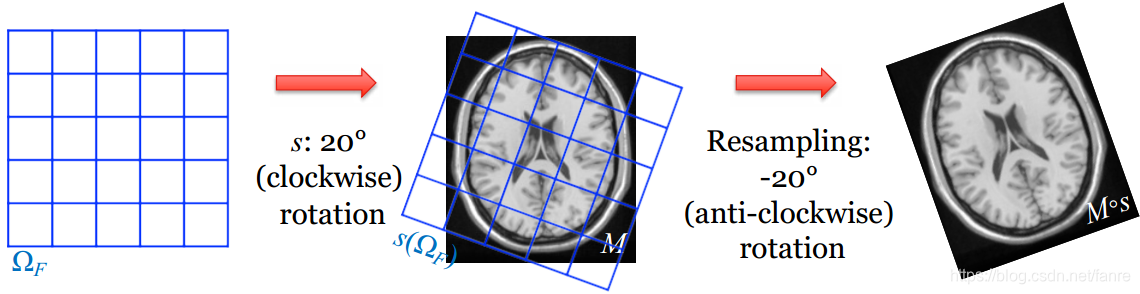

变换的方向

插值策略的影响

用小的旋转重采样多次:避免多次重采样!如果使用一次,线性插值是好的。